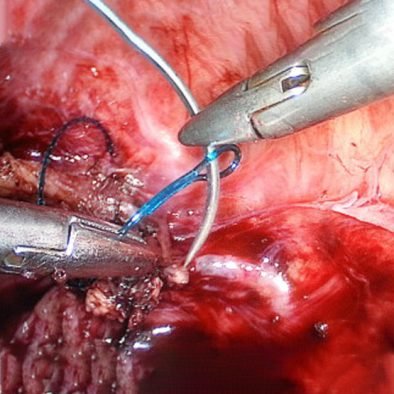

ByRL LAPAROSCOPIC NEEDLE HOLDER

Needle Holders are used to grasp and manipulate suture needles to enable free-hand Endo-suturing of wounds or surgical incisions with in the body during Laparoscopic procedures. These are used in almost all Laparoscopic Surgeries, Urology, General Surgery, Onco Surgery, Gynaecology, Gastroenterology, Bariatric / Obesity Surgery and Paediatric Surgery.

Product Features:

- The tungsten carbide jaws ensure stable, secure holding of the needle and suture material while still being highly resistant.

- The smooth-running, precisely settable ratchet facilitates secure positioning of the needle

- Antislip surface on handle provides firm and safe grip.

- Deeper slits on the jaws ensures firm and strong grip of needle and doesn’t allow slipping off the needle during endo-suturing.

- The ergonomic design of the handles allows relaxed and precise work

- A new needle holder with a needle righting function. The needle holder offers significant time and handling advantages, especially for interrupted suturing. The needle, which is clamped flat in the needle holder, can be raised at the site by means of the rotary wheel.

- Available in 4 types of Jaws:-

- Straight Jaws

- Self Righting Jaws

- Curved Jaws

- Toothed Jaw

- Available in sizes 3mm, 5mm and 10mm with length 30cm, 33cm & 43cm or any customised length